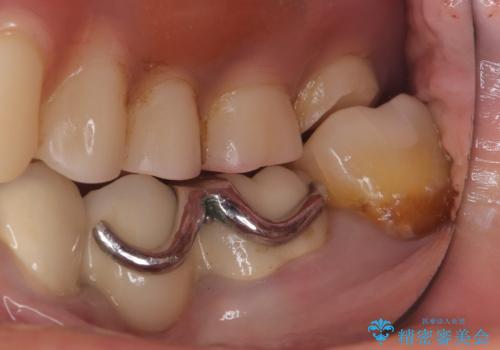

- 主訴:左下一番奥の銀の詰め物が外れてしまった。やり替えを機に綺麗なものを入れたい。

保険のメタルインレー脱離によるやり替え希望だったため、審美性・清掃性の良いセラミックインレーでのやり替えとなりました。

メタルインレー脱離後の窩洞をセラミックインレー窩洞に再形成し直し印象しています。遠心・舌側面のカリエスの除去、残存歯質の破折リスクを考えアンレー形態となりました。

アンレー装着時にはラバーダム防湿を行っています。